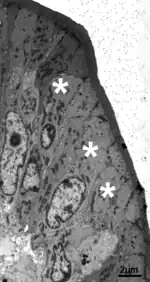

Microscopia Electrónica La ultraestructura del enterocito muestra orgánulos densamente empacados: numerosas mitocondrias, un retículo endoplasmático extenso, un aparato de Golgi grande y abundantes vacuolas y vesículas.

El borde en cepillo del polo apical está formado por microvellosidades, que son claramente visibles solo con grandes aumentos. Las microvellosidades son especializaciones de la membrana apical del enterocito.[2]

Con el microscopio electrónico las microvellosidades se observan como cilindros paralelos de 1 a 2 micrómetros (µm) de altura y 0,1µm de ancho;[1]

Por su eje central pasa un haz de filamentos que forman su esqueleto.